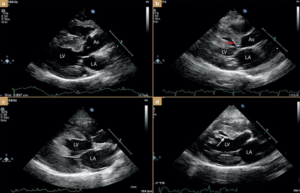

🔹 Ekokardiyografi (Ultrason) – Altın standart tanı yöntemidir.